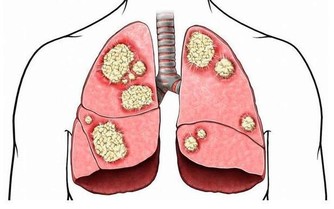

其實,骨質疏鬆和平時所用藥物也有關係,藥物長期使用之下可能造成骨質漸漸流失。

以下藥品有可能造成骨質流失,

因此若平時有長期使用以下藥品且確診為骨質疏鬆症患者,

建議與醫師聯繫,視情況調整用藥,才能做個有「骨氣」的人。